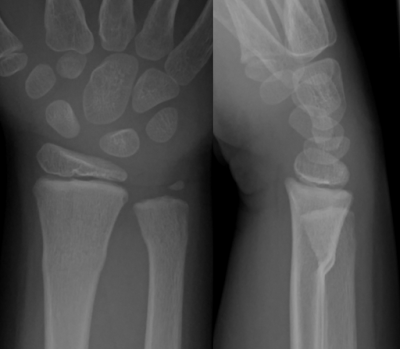

| another case: FOOSH, 6 years old girl |

- Wrist